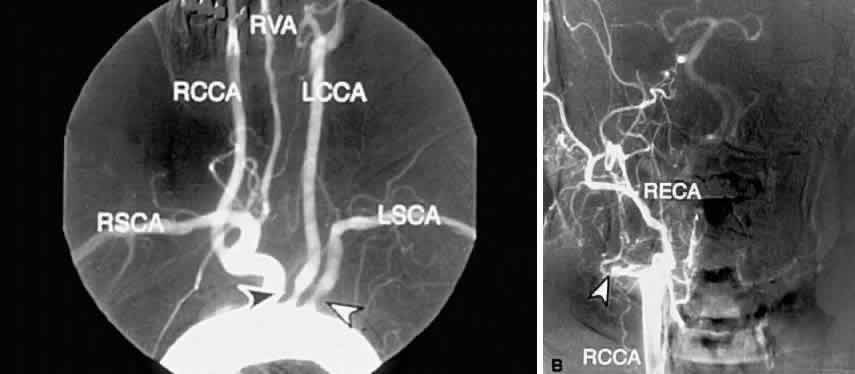

CAROTID ANGIOGRAPHY

Carotid angiography is performed by selective common carotid arterial injection of a radiopaque contrast dye via transfemoral catheterization. In the traditional technique, the image of the inner luminal silhouette is produced on x-ray emulsion (Fig. 10A and B). More recently, digital images and computerized image enhancement have improved resolution and reduced the amount of contrast dye required.46,47 This method can detect ulcerative lesions, severe stenosis, and formation of mural thrombus. It can also demonstrate collateral circulatory patterns.

Fig. 10. A. Digital subtraction aortogram revealing a 90% atherosclerotic stenosis of the proximal left common carotid artery (black arrowhead) and 80% stenosis of the proximal left subclavian artery (white arrowhead). RSCA, right subclavian artery; RCCA, right common carotid artery; RVA, right vertebral artery; LCCA, left common carotid artery; LSCA, left subclavian artery. B. Digital subtraction angiogram with a right common carotid injection from the same patient. There is complete occlusion of the right internal carotid artery due to atherosclerosis (white arrowhead). The right external carotid artery (RECA) and the right common carotid artery (RCCA) fill normally.

The most serious complications of carotid angiography are aortic or carotid artery dissection, embolic stroke, and myocardial infarction.48 Other complications include dye reactions, renal injury, hematoma, pseudoaneurysm, and arterial thrombosis. Carotid angiography carries a 1% risk of morbidity and 0.06% risk of mortality. As with all tests, the advantages of selective carotid angiography must be weighed against the possible risks.

Despite its expense and low but definite morbidity rate, carotid angiography remains the most reliable method of assessing atherosclerotic carotid disease,38 and it serves as the “gold standard” in the evaluation of all other tests of the carotid arteries.